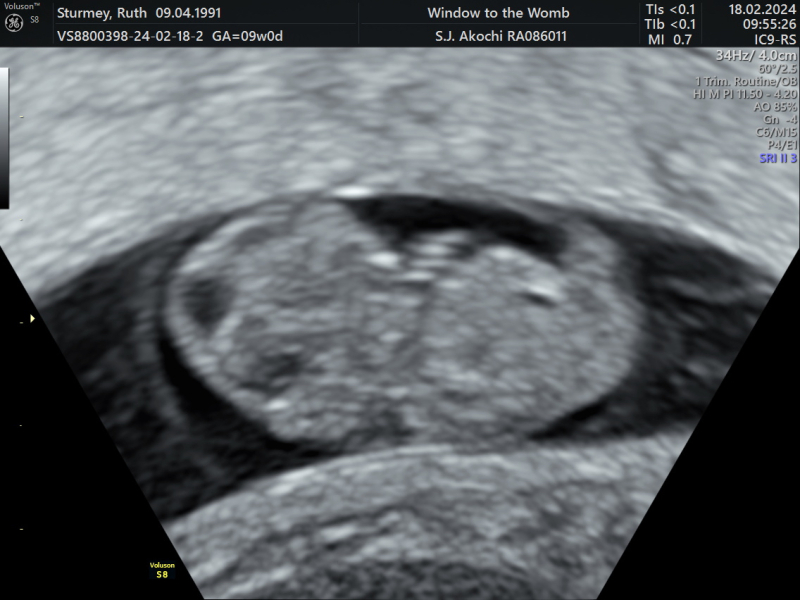

Went for a private scan this morning, twin has almost been fully reabsorbed and remaining baby has sped up some growing and is measuring 9 weeks exactly. Got to see it dancing around 💕 very relieved after some heavy bleeding this week!

MrsB2019x · 18/02/2024 15:02

Gorgeous scans ladies 😍😍😍

Oh all the scans are fab!! I also went for one on Saturday morning and baby measuring two days over so now 9+2 so feeling good and reassured 🥰

Amazing scans girls! I can’t believe we’re coming up to the 12 week mark already!